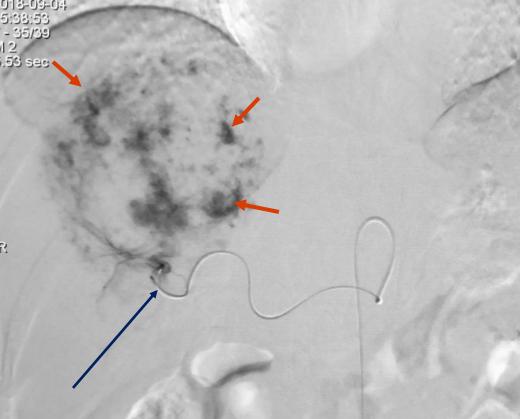

肝动脉造影显示肝内的肝癌病灶血供丰富

这是为什么呢?首先,肝癌被发现时,多数已经失去了手术切除的机会。其次,肝癌对全身化疗、放疗敏感性都不高。当然最重要的是,肝癌的介入疗效好。

因此,肝癌介入时,将混有化疗药的栓塞剂把供应癌肿的肝动脉分支完全栓塞,肝癌组织缺血缺氧,又遭受高浓度的化疗药物“浸泡”,自然就容易坏死;而正常肝组织并没有受到多少化疗药物的影响,而且由于有门静脉供血,正常肝组织也不至于缺血。因此,肝癌的“化疗栓塞”(TACE)就相当于用导弹定点打击敌人,所以才会疗效高、副作用小,自然就特别受欢迎。